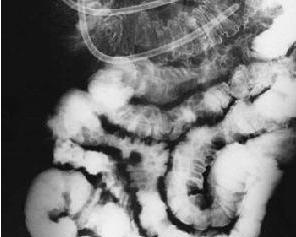

嵌杯样病毒胃肠炎是由嵌杯样病毒感染所引起,常暴发流行。6-12 岁儿童全部受染。全年均可发生,无明显流行季节。潜伏期 1-3天,以吐泻为主要症状。嵌杯样病毒(calicivirus)形态独特,直径30nm,表面环绕6个空洞,宛如嵌入6只杯子。故得此名,其中心部分也有一空洞。有5个血清型:UK1-4及日本的Sapporo 型。组织培养未成功。[1]